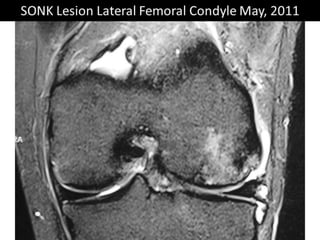

The document presents a detailed case study of a patient with transient osteoporosis of the hip (TOH) and spontaneous osteonecrosis of the knee (SONK) treated at Choithram Hospital & Research Centre in India. Over 20 years, the patient experienced multiple episodes of TOH and SONK with no history of trauma or co-morbidities, resulting in resolutions and recurrences of conditions. The information is intended for orthopedic surgery students and highlights personal experiences and case collections, with a disclaimer regarding content usage and potential controversies.